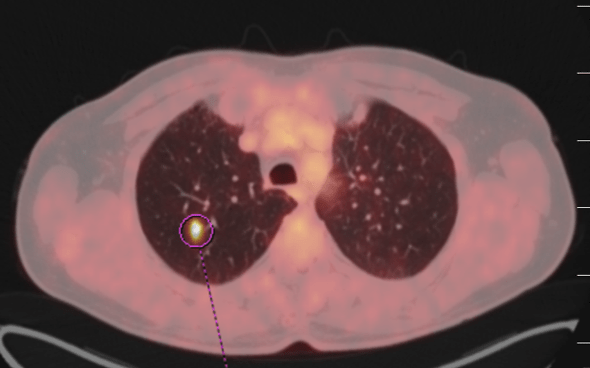

Pacient prošel multidisciplinární komisí, kde bylo onemocnění uzavřeno jak cT2 cN1 Mx s patologickou uzlinou v pánvi. Ale pro drobné plicní nodularity na bazích plic bylo doporučeno doplnit FDG PET/CT, které prokázalo patologické uzliny v pánvi a vícečetné plicní metastázy včetně ložiska v levém plicním hilu. Byla doplněna i bronchoskopie, která neprokázala bronchogenní tumor, bronchiální cytologie negativní.  V klinickém obraze se začínal rozvíjet mírný lymfedem obou dolních končetin. Dle prediktivního vyšetření TPS negativní, exprese PDL-1 méně než v 1% nádorových buněk, CPS pod 10. Celkově je pacient PS 1, občasné exacerbace CHOPN, dušnost při námaze, veden na plicní ambulanci.

Řez plicemi z CT screeningu: Stagingové PET/CT v 2/2021 potvrzuje plicní diseminaci.

Obr. 1Stagingové PET/CT v 2/2021 potvrzuje plicní diseminaci.